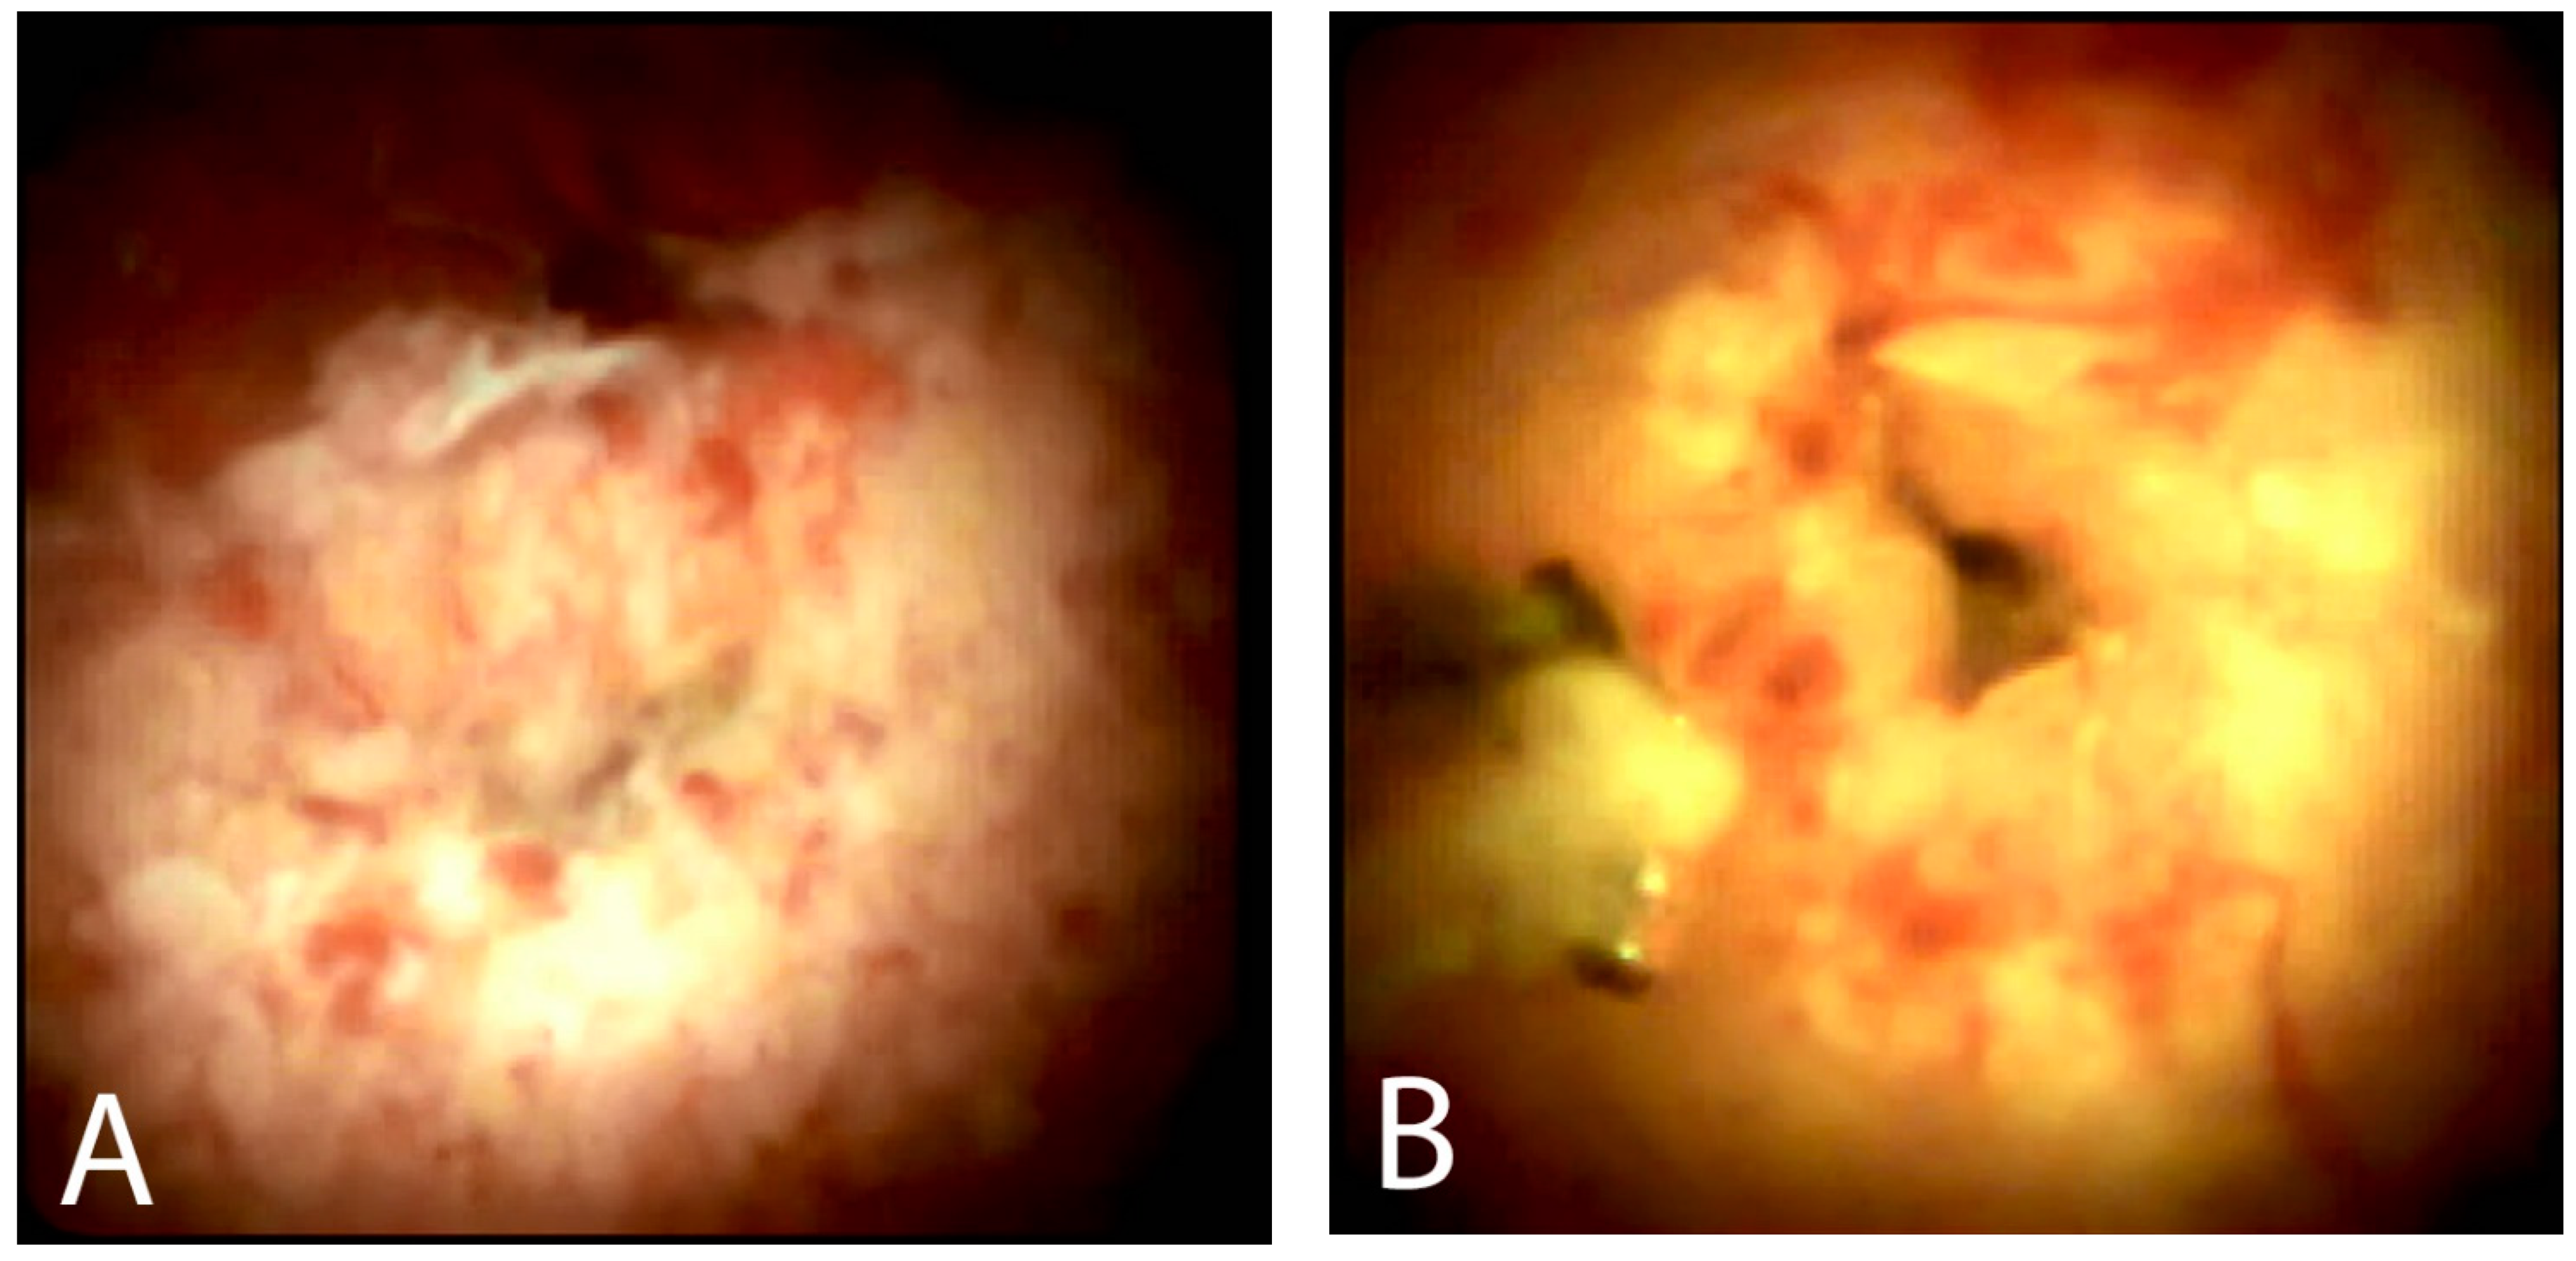

5.2. Visual Impression

5.3. Cholangioscopy-Guided Biopsy